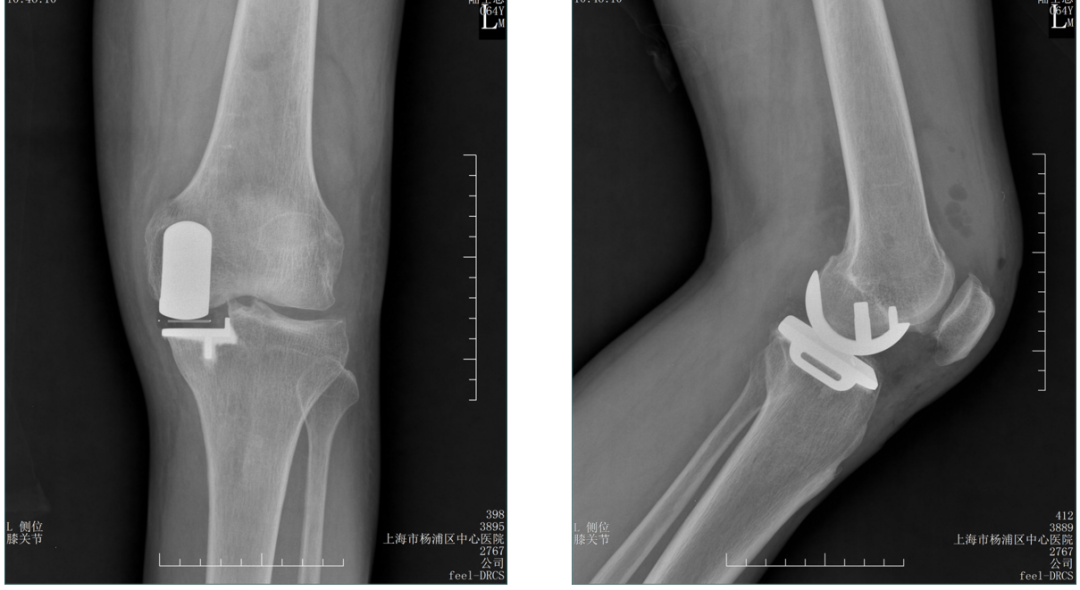

病例2:胫骨假体松动

病例2:单髁翻单髁

病例3:胫骨假体下沉

病例3:单髁翻单髁